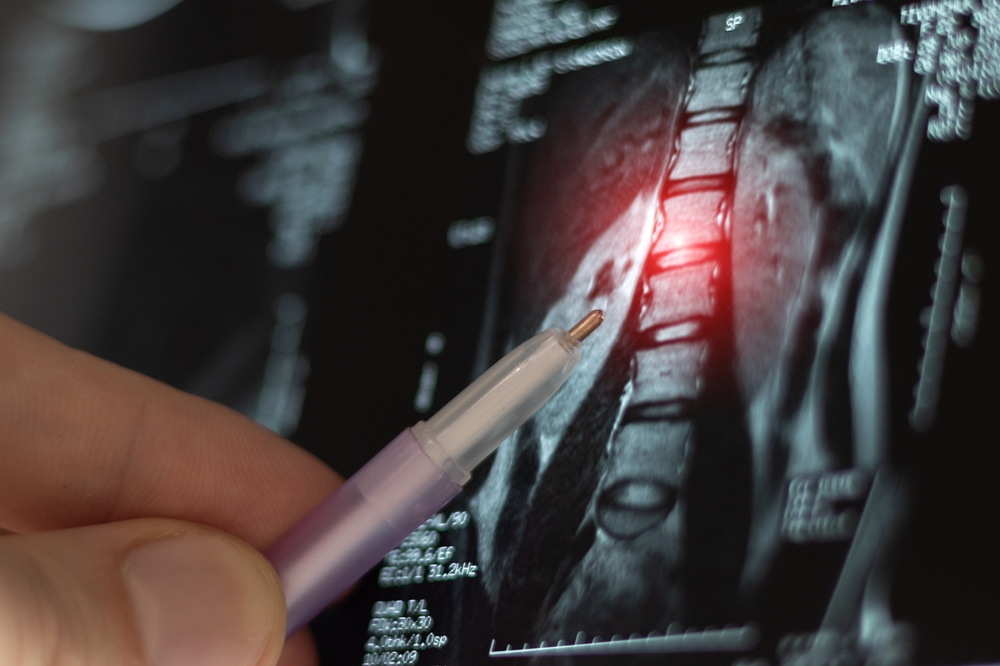

When your provider recommends imaging such as an MRI, it’s usually because they want a detailed look at what’s happening beneath the surface.

A spine MRI for back and neck pain near Chambersburg, Pennsylvania gives them that deeper insight.

Unlike X-rays, an MRI shows soft tissues clearly. It can detect herniated discs, nerve compression, spinal stenosis, inflammation, and other causes of persistent back or neck pain.